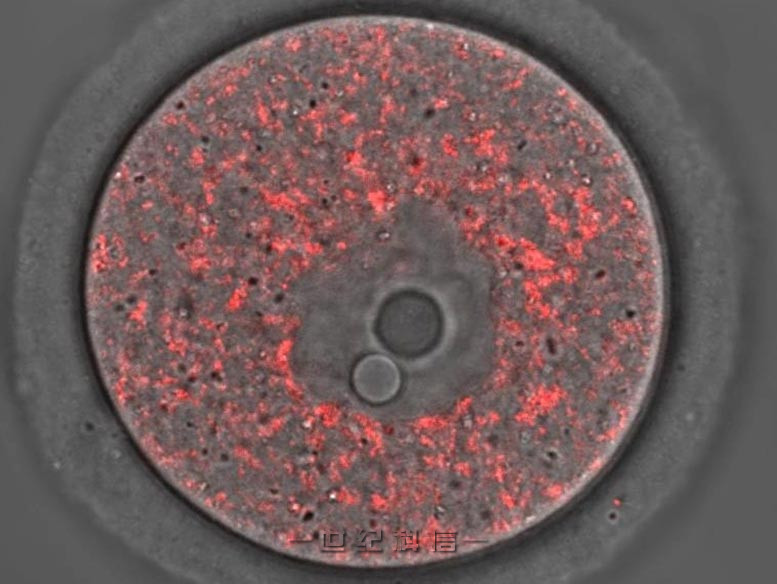

排卵前的未成熟小鼠卵子,线粒体染成红色。学分:马科斯·罗伯托·基亚拉蒂

该研究首次表明突变mtDNA在卵子形成的最后阶段积累。研究人员在小鼠身上进行了实验,报告称突变分子的比例随着卵子的成熟而增加,这些突变体会损害线粒体的功能,并导致疾病的发展。

对处于不同发育阶段的小鼠卵母细胞(未成熟卵子)的分析显示,m.5024C>T 水平高于野生型 mtDNA。这表明突变的 mtDNA 在卵母细胞成熟期间优先复制,无论细胞周期如何,因为卵子在排卵之前不会经历细胞分裂。